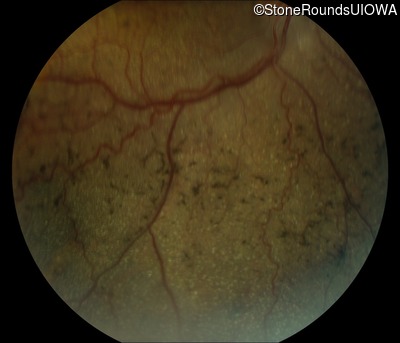

Fundus Montage - Right - 10/600

Exemplar

Fundus Montage - Left - 20/100 -2